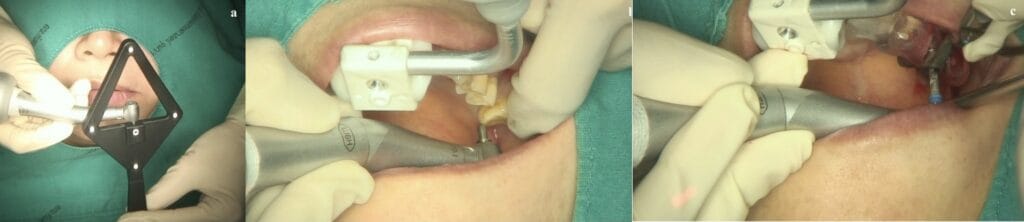

The use of the combined techniques is relatively simple if one has experience with both. At the left: the registration of the handpiece. Middle: registration of the drill tip and right: drilling with the surgical guide in place (right) and the splint with the fiducial markers of  the dynamic navigation system (left).

How can you combine static and dynamic? Well that was not too difficult actually. In principle, you have to follow the workflow of the static, print the guide accordingly and then register and calibrate the guided surgery drills for the dynamic CAIS before the surgery. In the surgery the operator will place the surgical guide and continue with the drills as usual, only now with the visual aid of the correct angle and depth also displayed in real time.